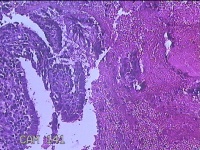

子宫腔内容物

性别

女

年龄

46岁

临床诊断

子宫异常出血;子宫肌瘤多发性;附件囊肿;梅毒

一般病史

不规则阴道流血10天。

标本名称

大体所见

纱布一块,内有灰白暗红色不规则碎组织3.5x2.3x0.5cm一堆。